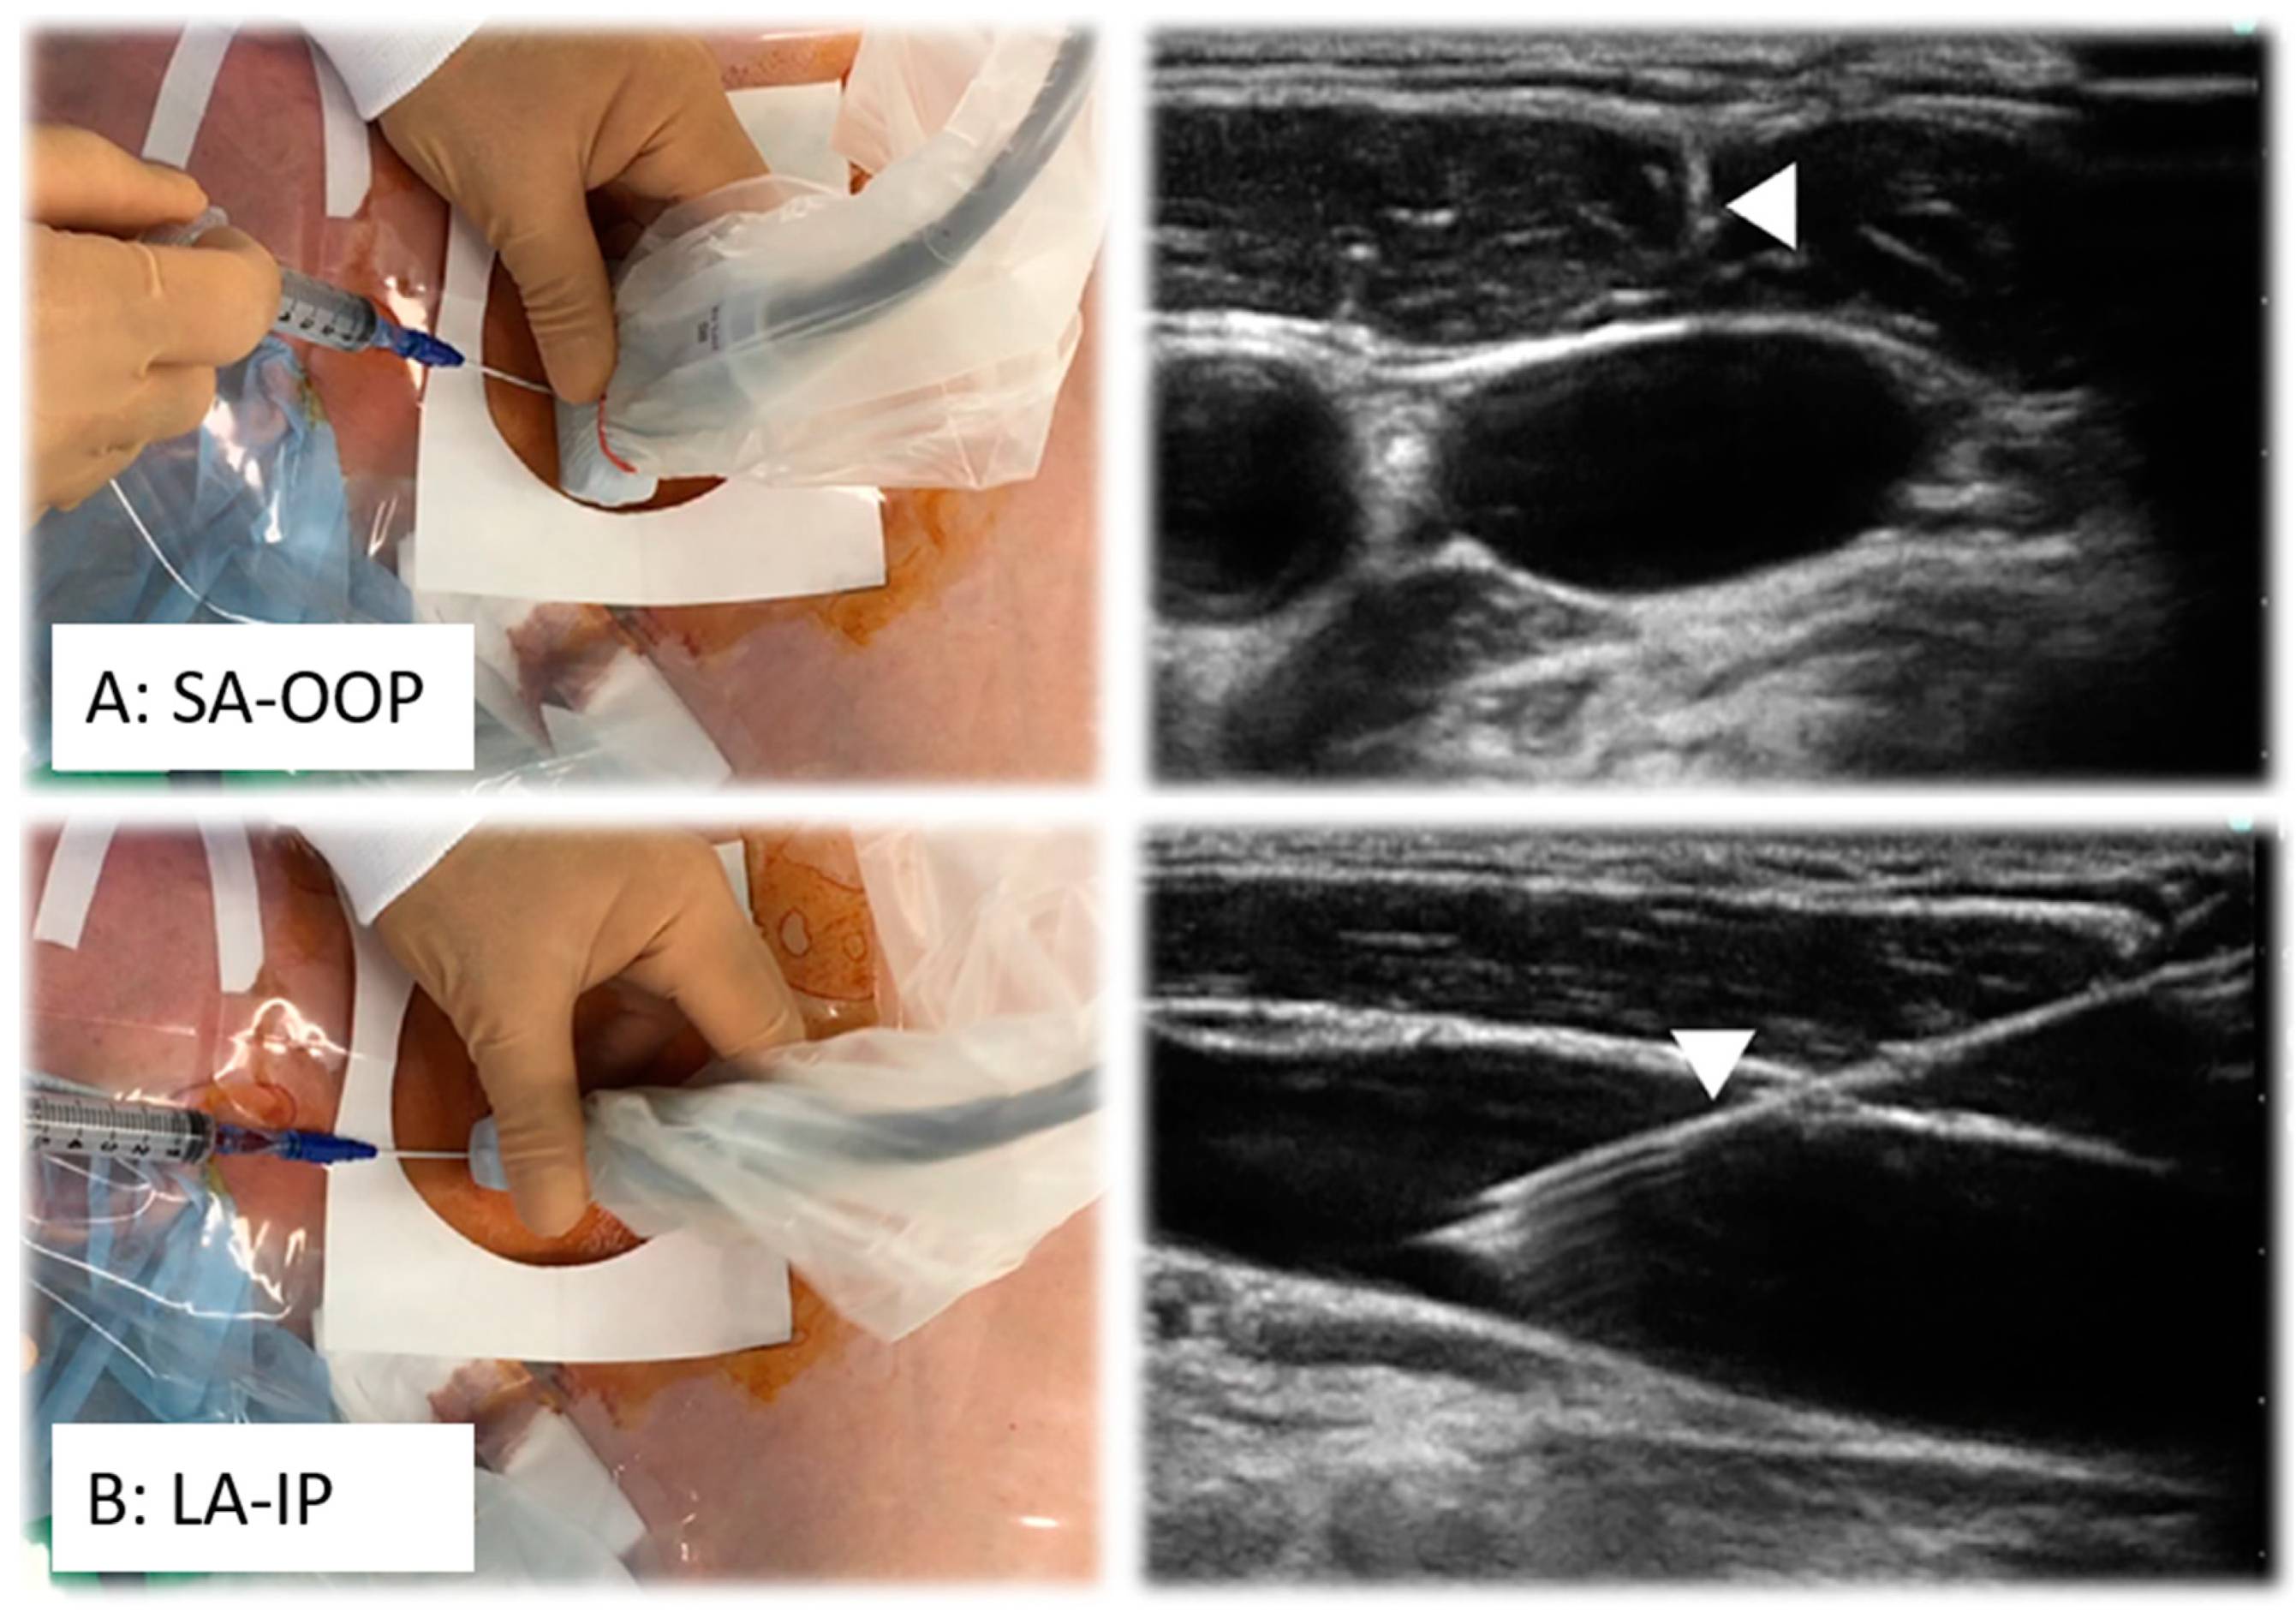

Continuous needle visualization significantly reduces the number of punctures and the risk of complications by ensuring proper alignment of the US probe [12]. Two primary 2D single-plane methods guide this alignment: the short-axis out-of-plane (SA-OOP) approach and the long-axis in-plane (LA-IP) approach. The SA-OOP method displays the vessel as a circular cross-section with the needle perpendicular to the US beam, enhancing patient comfort due to a shorter needle path (Figure 3) [6,7]. On the downside, distinguishing the needle tip from the shaft becomes more challenging as the needle advances and increases the risk of PWP of adjacent vessels. In the LA-IP approach, the vessel appears in a longitudinal section as a truncated tube. The needle is seen as one white line, making it easier to follow, as in SA-OOP. In the LA-IP view, the needle has a longer path to travel and, therefore, causes more discomfort to the patient.

Figure 3.

Schematic view of the long-axis in-plane (LA-IP) and short-axis out-of-plane (SA-OOP) approaches for needle (arrow) guidance. Adapted from [6] with permission from Elsevier.